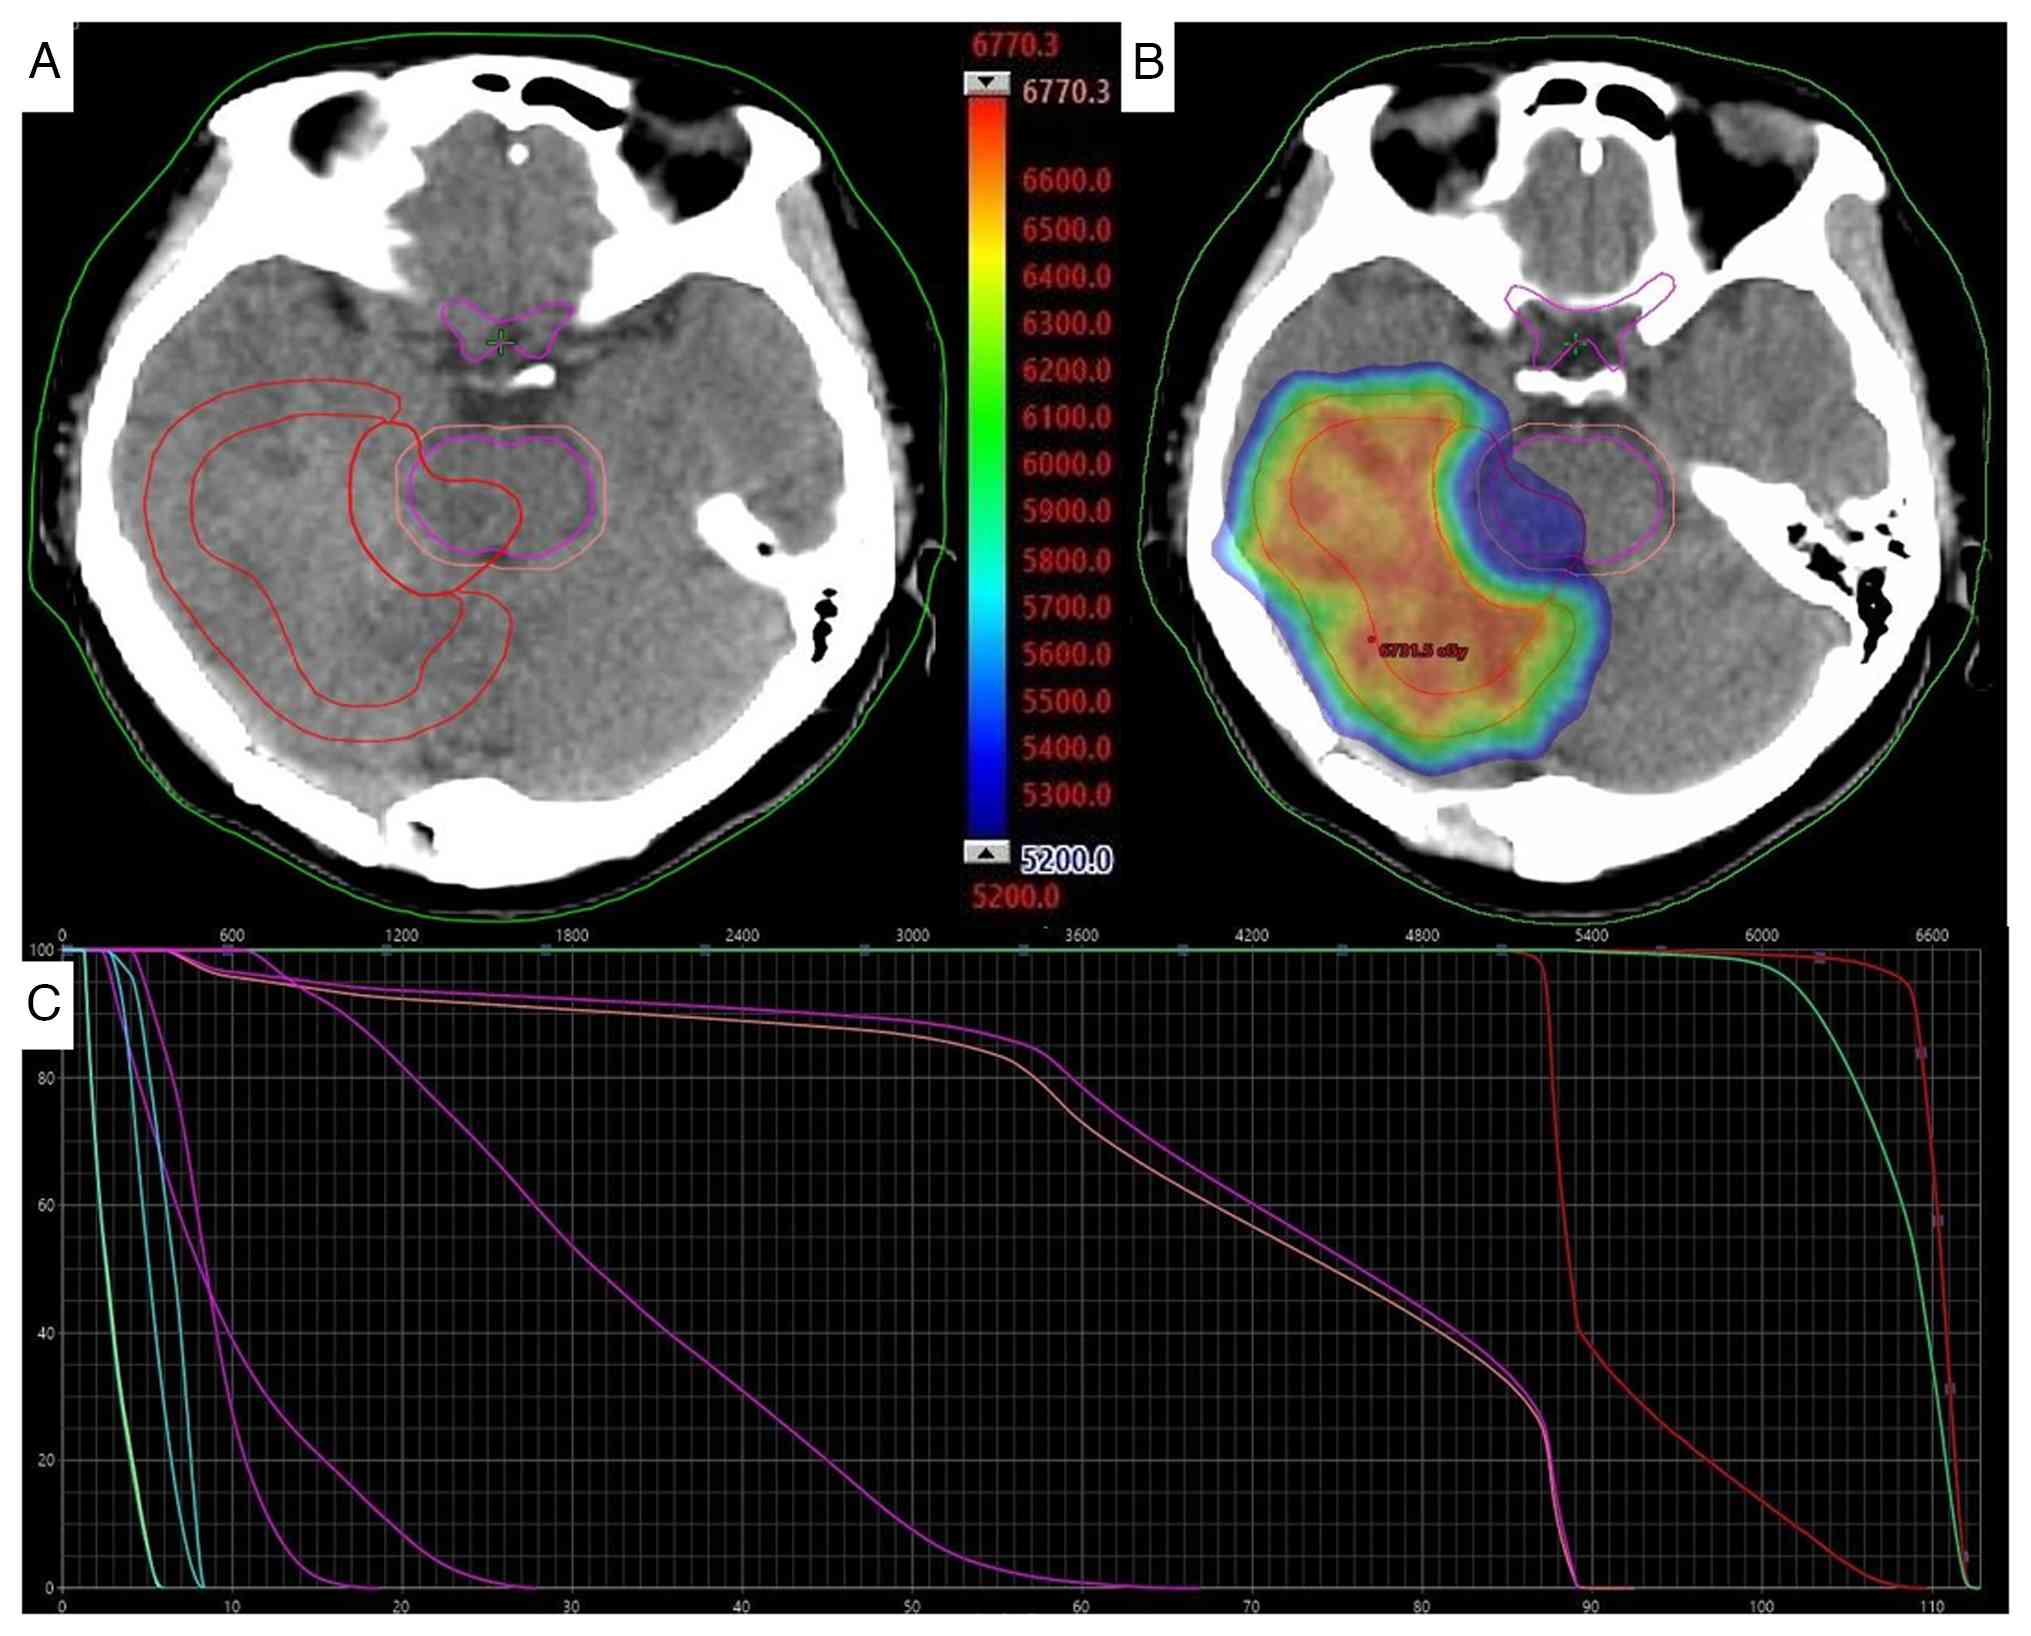

Before radiotherapy, a head CT scan was performed using a helical tomotherapy system (Accuray, Inc.). The scanning parameters were as follows: The patient was positioned in a supine position, utilizing helical scanning with a tube voltage of 120 kV, tube current ranging from 200 to 250 mAsec and a slice thickness of 1 mm. The scanning range extended 2 cm from the upper edge of the parietal scalp to the lower part of the skull base. This scan was conducted for radiotherapy localization. The patient subsequently received adjuvant IMRT concurrent with daily oral temozolomide at a dose of 100 mg for a total of 38 days. The planning target volume (PTV) for the postoperative bed (PTV1) received 6,500 cGy in 30 fractions, while the adjacent brainstem region (PTV2) received 5,200 cGy (max dose, 5,358.8 cGy) (Fig. 5). Supportive care included intravenous administration of 20% mannitol (a routine dehydrating agent for cerebral edema) at a dose of 250 ml per infusion, administered every 8 h (1–2 g/kg body weight) via rapid intravenous drip (completed within 30–60 min), for a total of 38 consecutive days.

Intracranial lesion radiotherapy

treatment plan. (A) Target delineation: The GTVs were defined as

GTV-65 (intracranial lesions outside the brainstem) and GTV-53

(brainstem lesions). The planning target volumes were generated by

expanding the respective GTVs by 0.8 cm, and the brainstem

interface was not expanded. (B) The dose distribution was shown on

the axial computed tomography slices with equal dose, and the total

dose was 6,731.5 cGy. (C) Dose-volume histogram of target volume

and organs at risk; dosage limits for dangerous organs follow the

Radiation Therapy Oncology Group guidelines (18). GTV, gross tumor volume.

Figure 5.

Intracranial lesion radiotherapy treatment plan. (A) Target delineation: The GTVs were defined as GTV-65 (intracranial lesions outside the brainstem) and GTV-53 (brainstem lesions). The planning target volumes were generated by expanding the respective GTVs by 0.8 cm, and the brainstem interface was not expanded. (B) The dose distribution was shown on the axial computed tomography slices with equal dose, and the total dose was 6,731.5 cGy. (C) Dose-volume histogram of target volume and organs at risk; dosage limits for dangerous organs follow the Radiation Therapy Oncology Group guidelines (18). GTV, gross tumor volume.